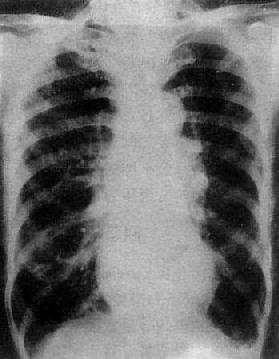

慢性肺原性心脏病

图3-2-17 慢性肺原性心脏病

心呈二尖瓣型,右心室增大,肺动脉突出,但无左心耳增大。肺动脉扩张,尤以右下肺动脉为明显,有肺门截断现象,说明有肺动脉高压肺纹理增强,肺透明度增加,膈平而低,说明有慢性支气管炎肺气肿